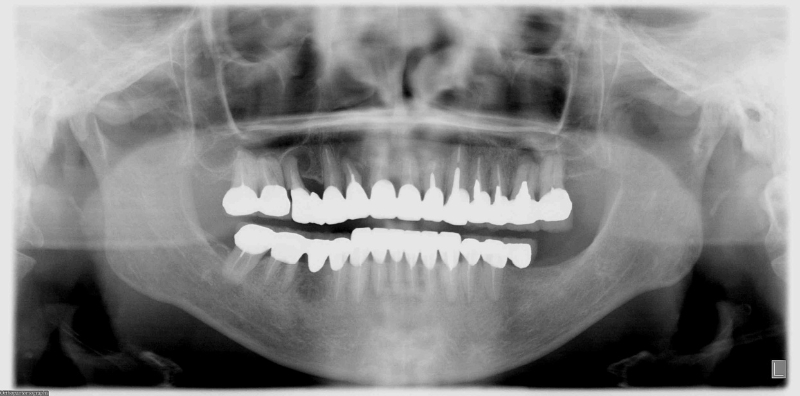

<症例2>60歳代 男性

長年放置したために歯周病が進行し噛みにくくなった患者様が、インプラントを入れ全顎的な治療を行い、審美改善しました。

正面

レントゲン写真